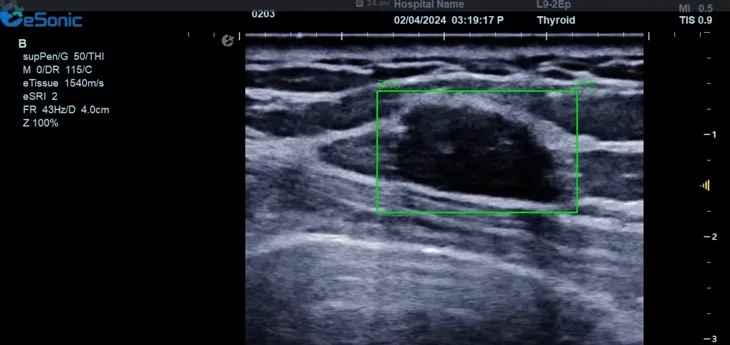

3377体育医疗(ESI)表示,其最新的人工智能功能可以帮助到医疗机构的工作效率,功能包括,实时、动态、快速自动识别病灶,良恶性病灶概率预测,甲状腺结节和乳腺的二维灰阶动态自动实时检测需求,提供多个结节动态检测轮廓框。实时获取多幅具备临床特征(大小、属性等)的结节切面,同时提供当前切面所示结节的结节大小、属性特征、TI-RADS 分级。

对于甲状腺结节相关的自动检测功能,甲状腺结节病灶检出率≥95%,良恶性分类灵敏度≥90%、良恶性分类特异度≥85%。